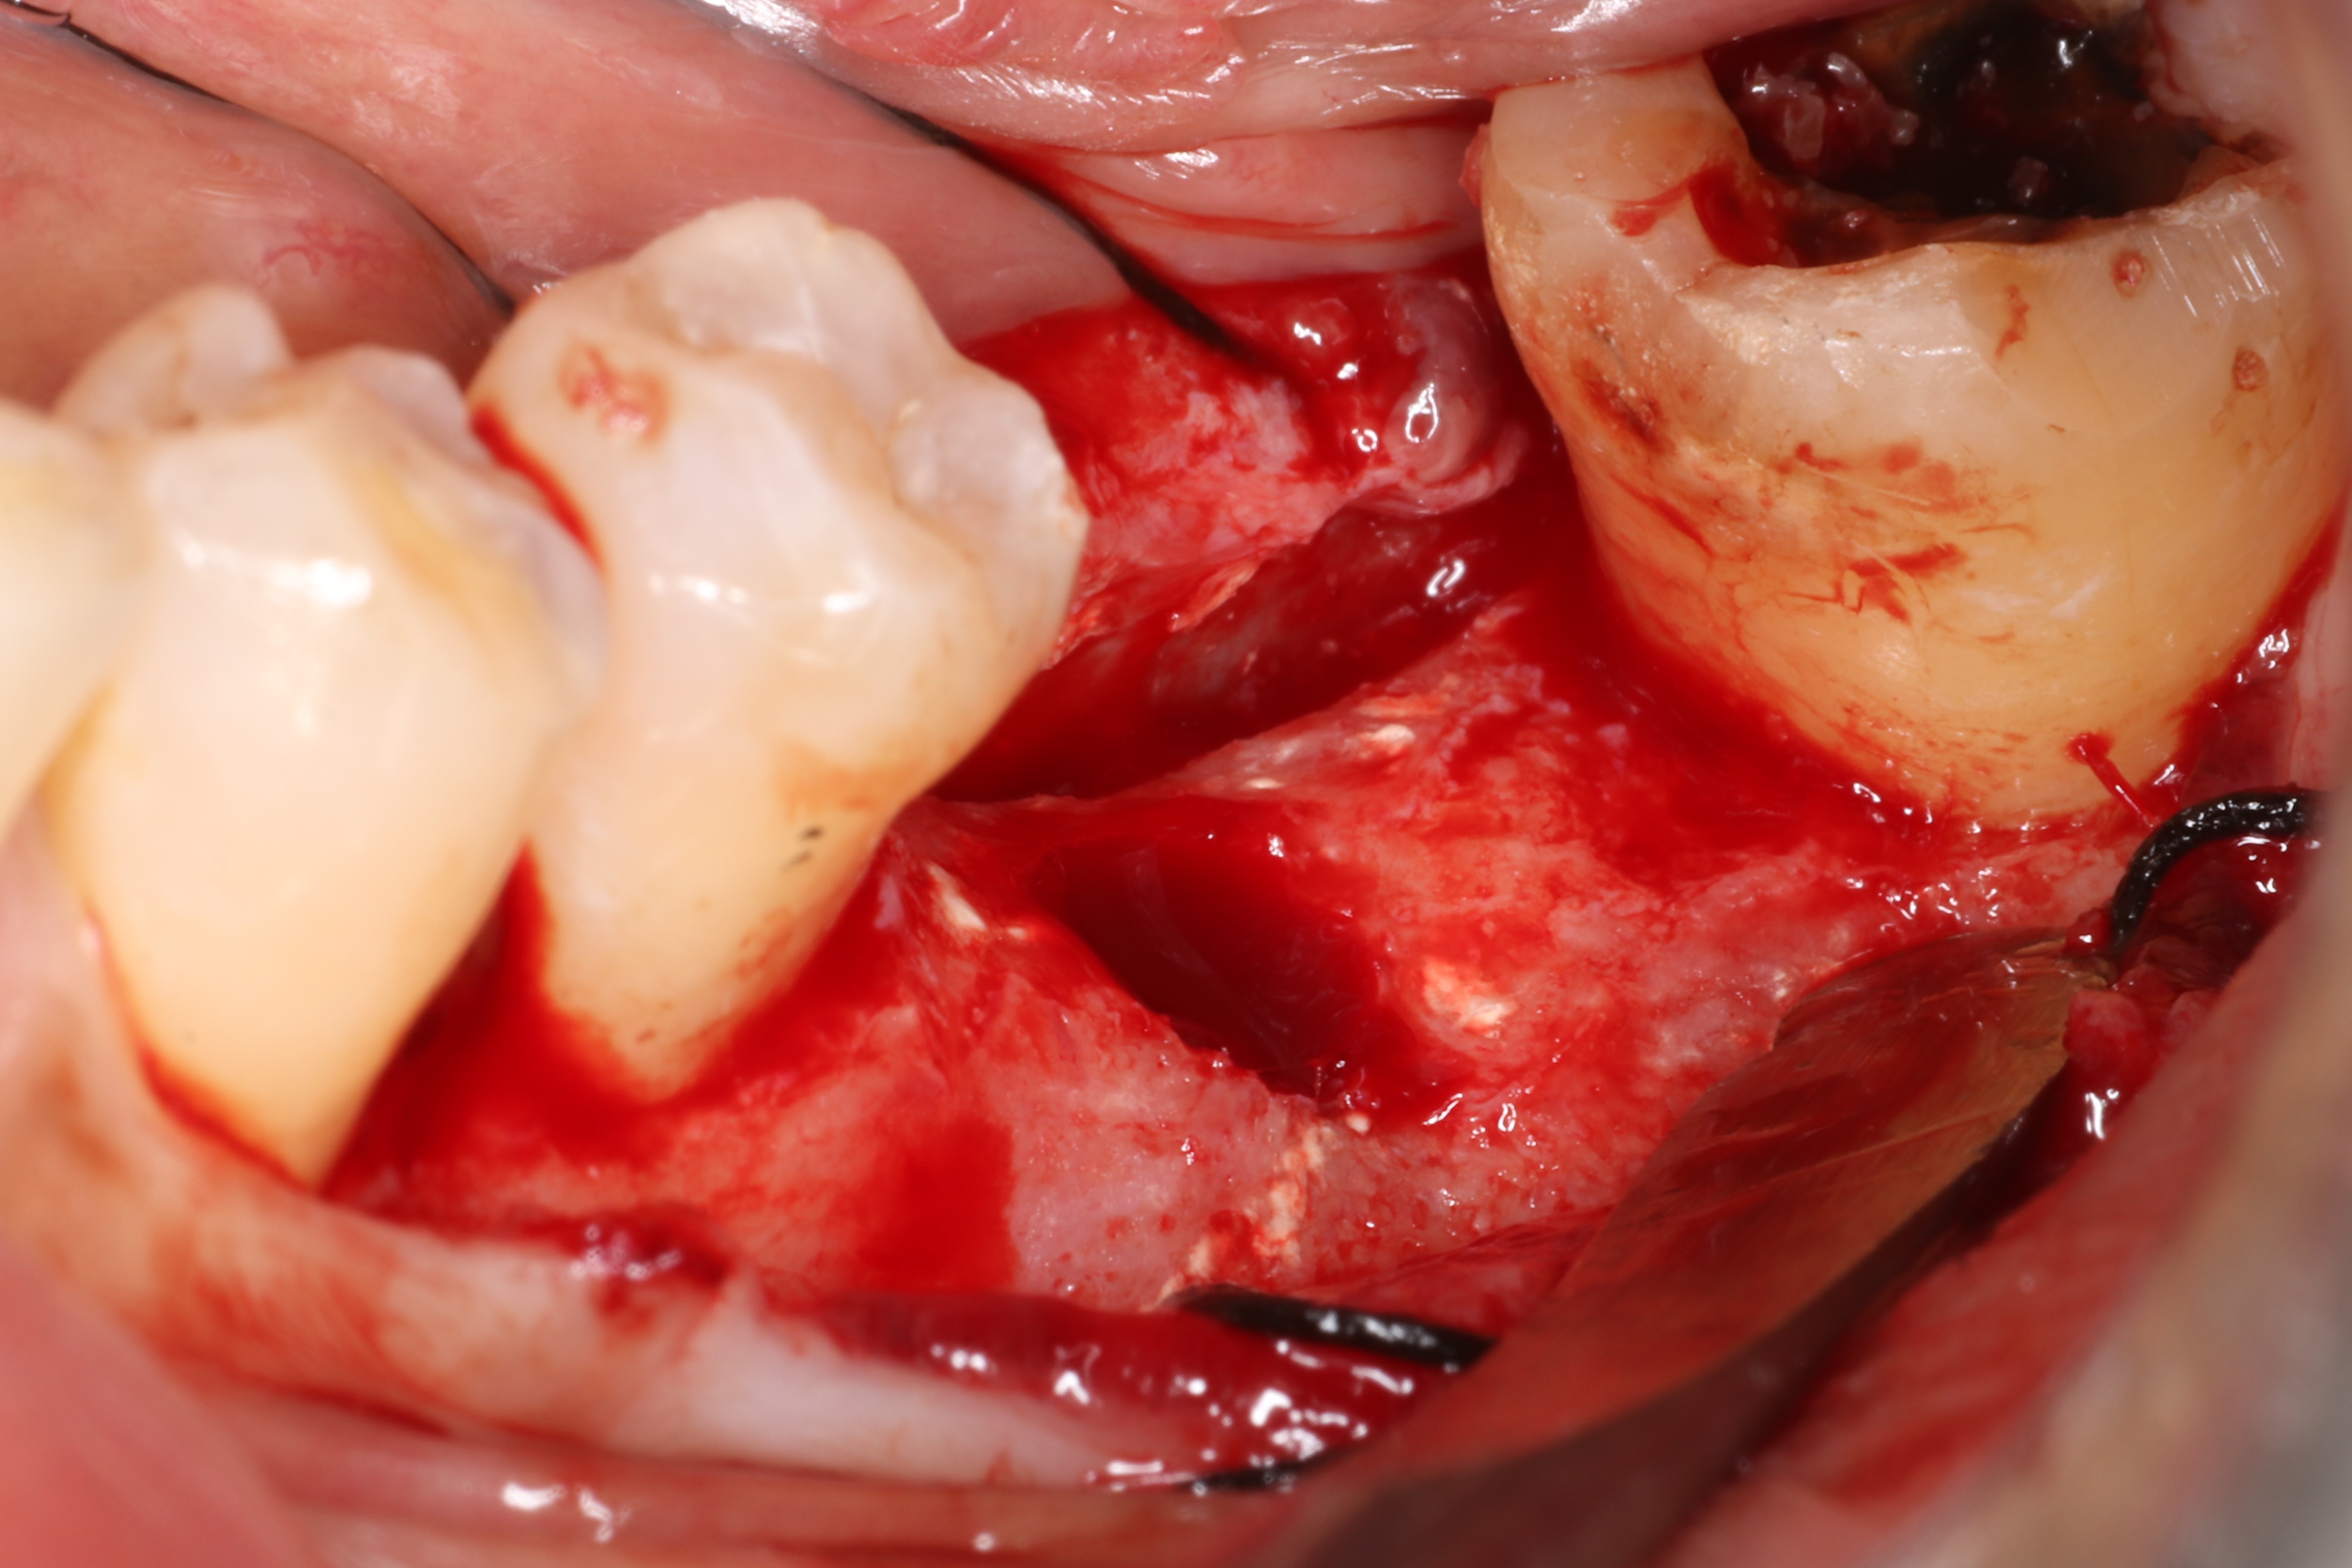

這個案例,最早沒把握能救回來,但是做完非手術治療,發現恢復非常好。

於是大膽地請矯正與假牙專科醫師一起幫忙完成。其實病人本身也同意,若途中狀況不好,還是得拔除。我知道這種案例,其實對其他專科來說,可能是有壓力的,不容易處理,也是難症。

好佳在,兩位神隊友都完成了,非常感謝合作專科的信任,還有,病患六年來維持得非常好,目前囊袋正常、零出血、零發炎。

回頭看,一開始就拔掉牙齒,改走其他路線,或許也可以,每位醫師選擇的或許不一樣,並沒有標準答案。

但是,能幫病患留下自己的牙齒,真的是很開心的一件事~~